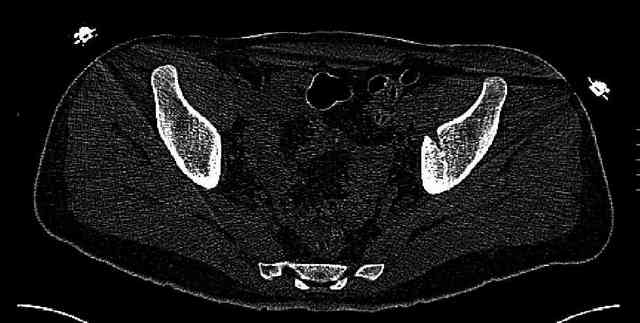

Some more images. Does it help to guess which part of the acetabulum is displaced?

Normal appearing SI joints and a healed posterior column limb... my bet's on caudal segment displacement.